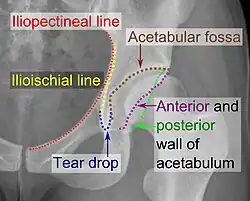

The hip joint is a ball and socket synovial joint formed by the articulation of the rounded head of the femur and the cup-like acetabulum of the pelvis.[5] The socket of the acetabulum is pointing downwards and anterolaterally. The socket is also turned such that the outer edge of its roof is more lateral than outer edge of the floor.[5] It forms the primary connection between the bones of the lower limb and the axial skeleton of the trunk and pelvis. Both joint surfaces are covered with a strong but lubricated layer called articular hyaline cartilage.

The cuplike acetabulum forms at the union of three pelvic bones — the ilium, pubis, and ischium.[6] The Y-shaped growth plate that separates them, the triradiate cartilage, is fused definitively at ages 14–16.[7] It is a special type of spheroidal or ball and socket joint where the roughly spherical femoral head is largely contained within the acetabulum and has an average radius of curvature of 2.5 cm.[8] The acetabulum grasps almost half the femoral ball, a grip deepened by a ring-shaped fibrocartilaginous lip, the acetabular labrum, which extends the joint beyond the equator.[6] The centre of the acetabulum (fovea) does not articulate to anything. Instead, it is lined with fat pad and attached to ligamentum teres. The acetabular labrum is horse-shoe shaped. Its inferior notch is bridged by transverse acetabular ligament.[5] The joint space between the femoral head and the superior acetabulum is normally between 2 and 7 mm.[9]

The acetabulum is oriented inferiorly, laterally and anteriorly, while the femoral neck is directed superiorly, medially, and slightly anteriorly.

Wiberg's centre-edge angle (CE angle) is an angle between a vertical line and a line from the centre of the femoral head to the most lateral part of the acetabulum,[13] as seen on an anteroposterior radiograph.[14]